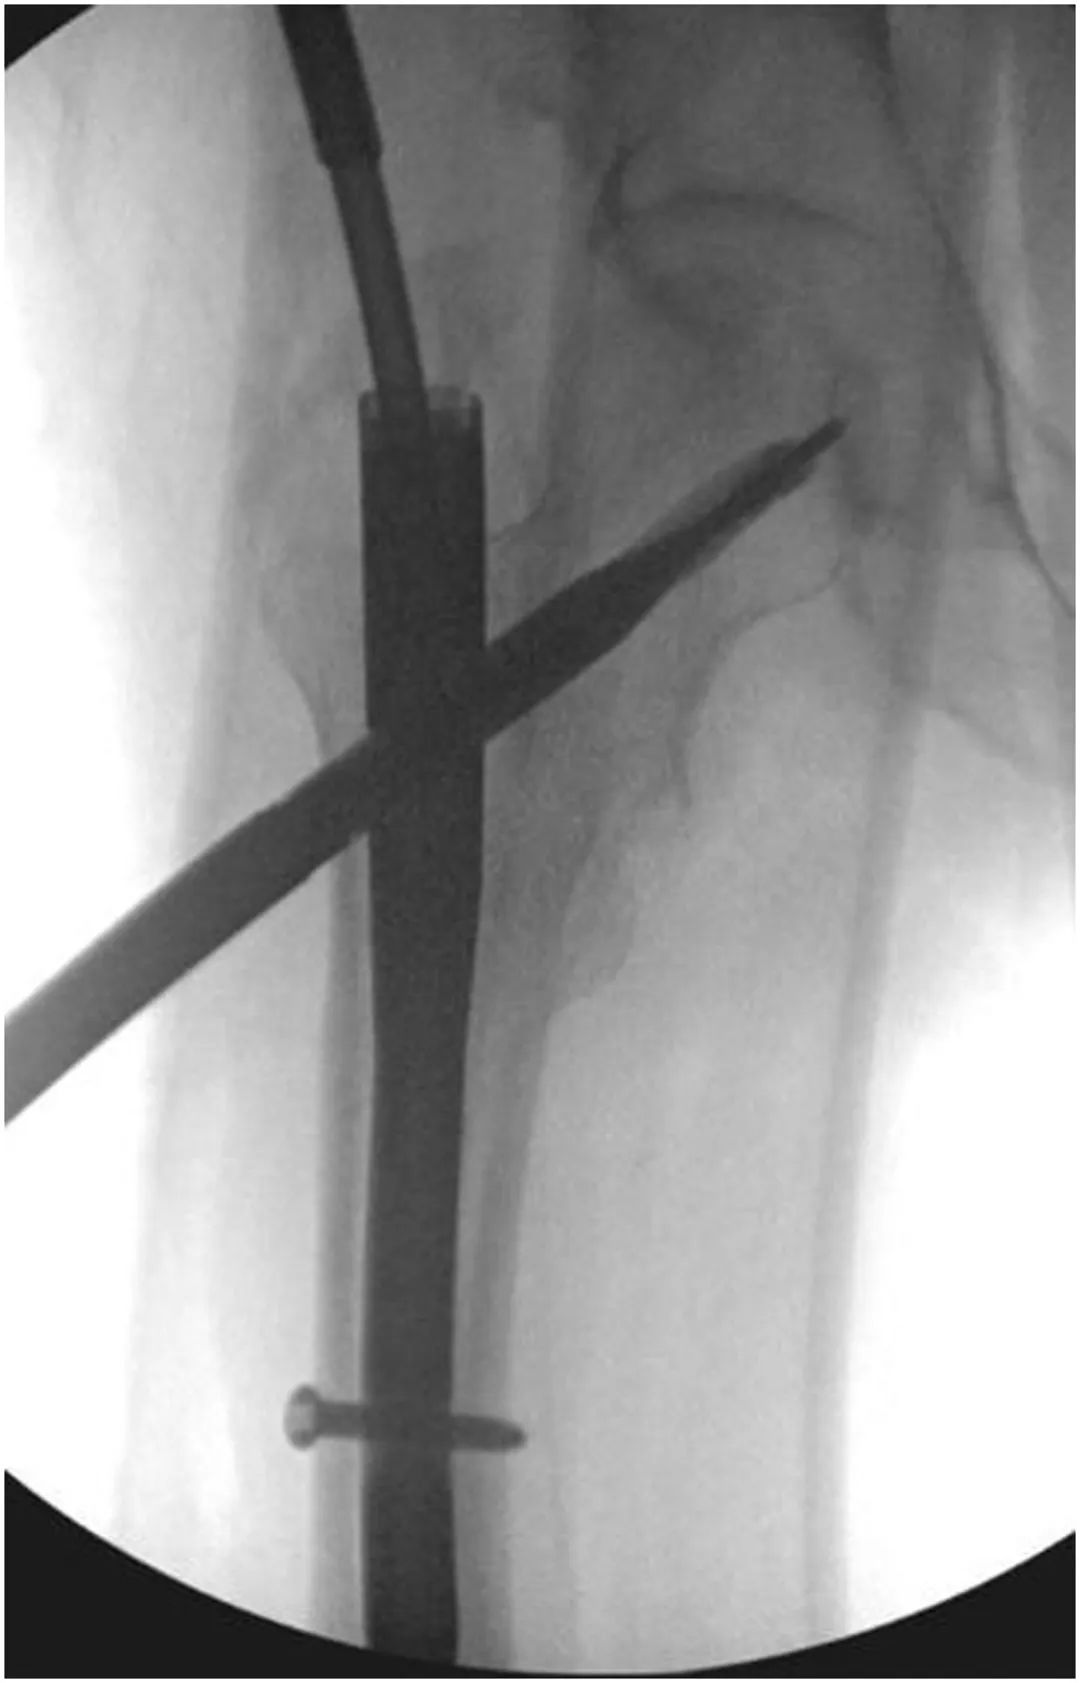

Затем в субхондральную кость головки бедренной кости по оси шейки бедренной кости вводят новый винт или спиральную лопасть, следя за тем, чтобы не проникнуть в головку (рис. 4).Винт намеренно вводят, избегая прохода предыдущего стержня, но по-прежнему направляя его конец к центру головки бедренной кости.(Рисунок 5)

Рисунок 5, интраоперационная рентгеноскопия, показывающая введение нового цефаломедуллярного лезвия вдоль пути проводника, которое впоследствии было затянуто установочным винтом.